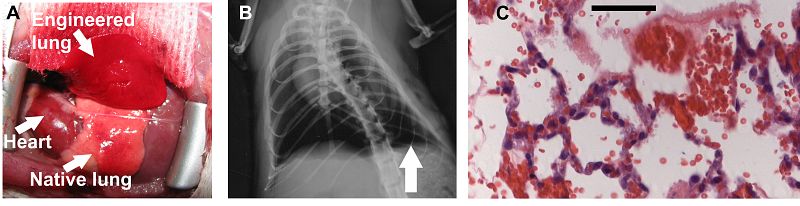

La Transplantation Society (TTS) de EE.UU y la Organización Nacional de Trasplantes (ONT) de España han obtenido el Premio Príncipe de Asturias de Cooperación Internacional. El fallo destaca la 'cooperación' entre ambas instituciones y su 'labor determinante en el establecimiento de los principios médicos y éticos que siguen la investigación científica y la práctica clínica' para la realización de trasplantes en todo el mundo. El doctor Josep María Carals, uno de los pioneros en los transplantes de corazón en España, asegura en esta entrevista con Radio 5 que el premio favorecerá las donaciones de órganos (16/06/10)

Cinco mil personas fallecen al año esperando un órgano para ser trasplantado. Las Asociaciones de trasplantados de corazón cren que el premio Príncipe de Asturias ayudará a rebajar esta cifra. También creen que servirá para impulsar la investigación y la cooperación internacional, como nos ha explicado Emilio Bautista, presidente de la Federación española de trasplantados de corazón (16/06/10)

La Organización Nacional de Trasplantes de España (ONT) y la Transplantation Society (TTS), con sede en Canadá y una de las primeras sociedades dedicadas a promover la donación de órganos en todo el mundo, han obtenido hoy de forma conjunta el Premio Príncipe de Asturias de Cooperación Internacional 2010. La propuesta para premiar a ambas entidades se impuso en las últimas votaciones a las candidaturas de la Red de Jóvenes Afectados por la Guerra, organización dedicada a ayudar a los niños soldado, y de la fundación alemana Alexander Von Humboldt (16/06/2010).

Más de dos millones de donantes salvan, en España, a 27 mil personas al año y hacen que 130 mil recuperen su salud.